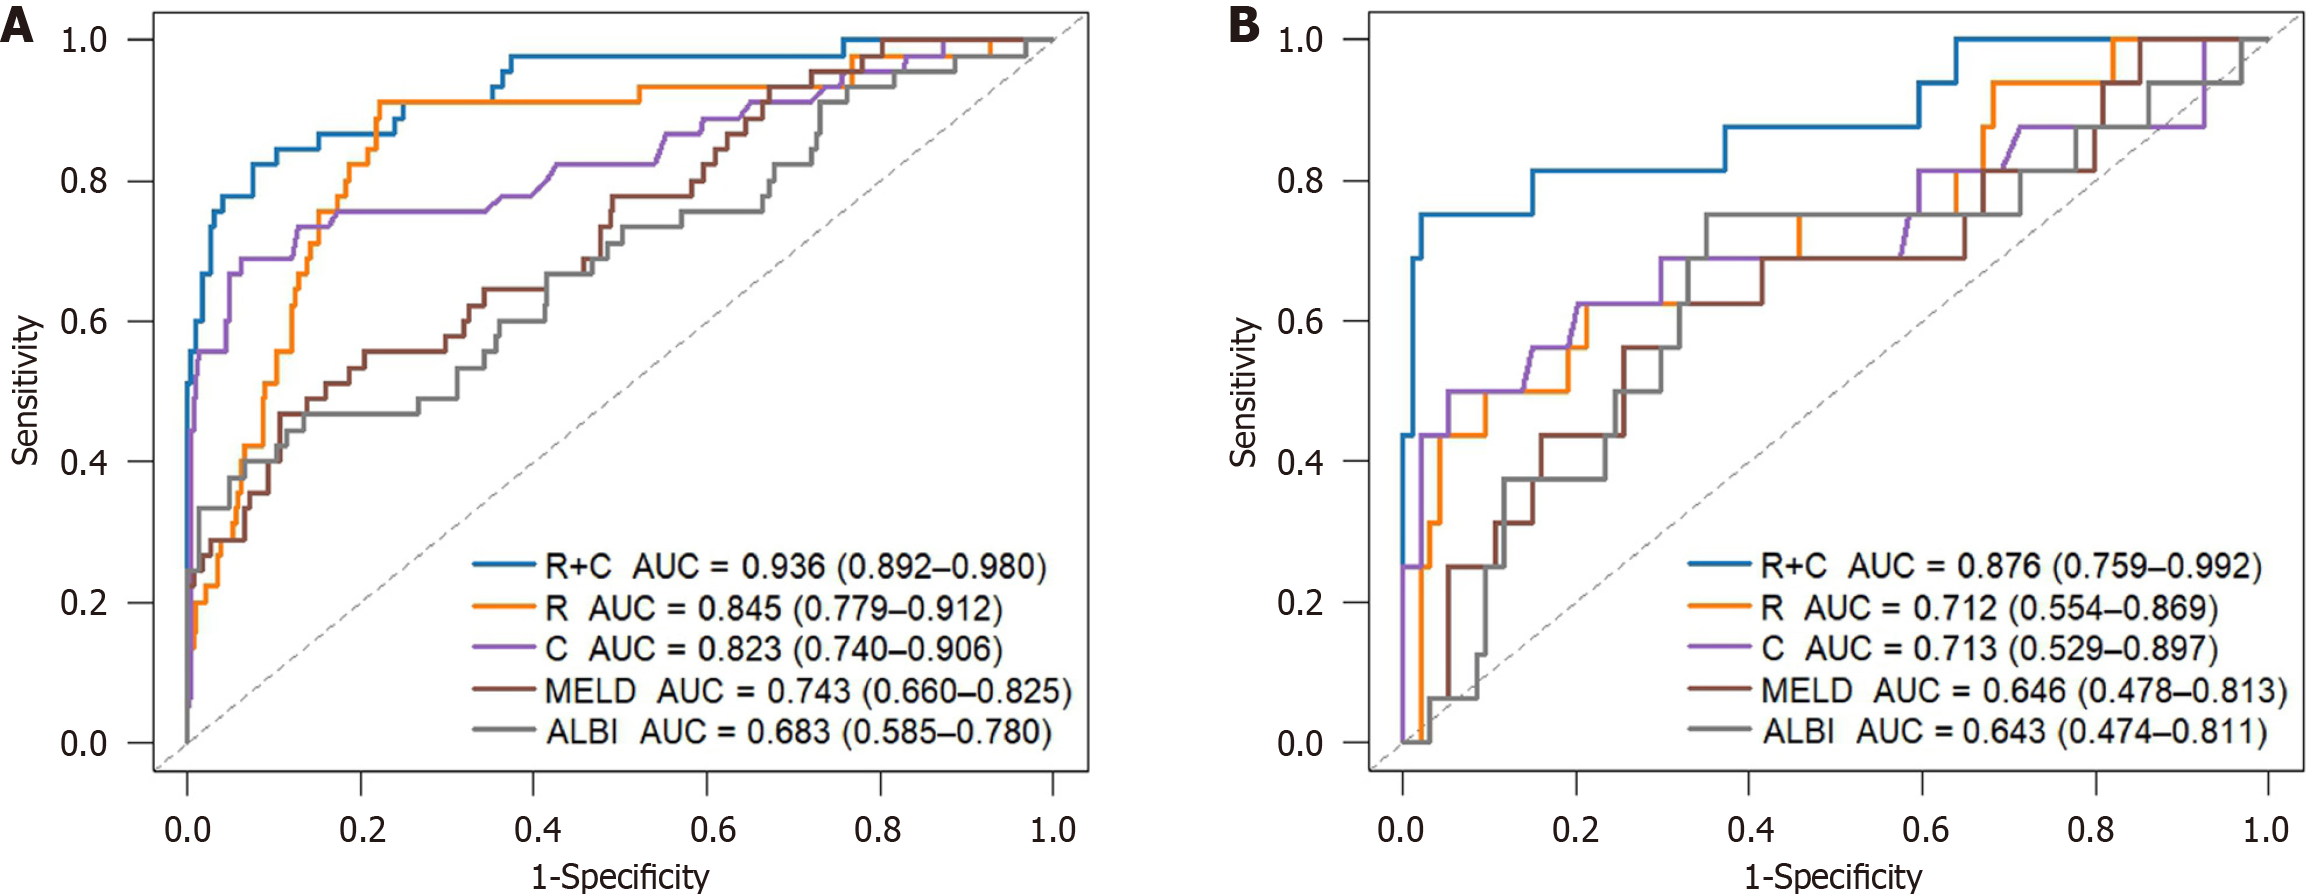

The Radscore comprised four hepatic and six splenic CT features, which predicted the risk of variceal bleeding. Multivariate analysis identified invasive treatment to relieve hepatic venous outflow obstruction, anticoagulant therapy, and hemoglobin levels as independent clinical predictors. The R + C model achieved C-indices of 0.906 (training) and 0.859 (validation), outperforming the radiomics and clinical models alone (AUC: training 0.936 vs 0.845 vs 0.823; validation 0.876 vs 0.712 vs 0.713). DCA showed higher clinical net benefit across the thresholds. The model stratified patients into low-, medium- and high-risk groups with significant differences in bleeding rates (P < 0.001). An online tool is available at https://bcsvh.shinyapps.io/BCS_Variceal_Bleeding_Risk_Tool/.

To construct a comprehensive risk prediction model, the radiomics-based Radscore was integrated with significant clinical variables identified through multivariate Cox regression analysis. The final model revealed that the following were independent risk factors for bleeding in patients with BCS. Invasive treatment to relieve hepatic venous outflow obstruction [hazard ratio (HR) = 0.089, 95%CI = 0.044-0.181, P < 0.001), use of anticoagulants (HR = 10.653, 95%CI = 3.102-36.582, P < 0.001), gender (HR = 2.332, 95%CI = 1.057-5.144, P = 0.036), platelet count (HR = 0.992, 95%CI = 0.984-0.999, P = 0.035), and Radscore (HR = 1.545, 95%CI = 1.236-1.932, P < 0.001). These variables were incorporated into a nomogram for individualized prediction (Figure 4). The predictive accuracy of the radiomics + clinical (R + C) model was assessed using the C-index, which achieved values of 0.906 in the training set and 0.859 in the validation set, indicating excellent discrimination. The R + C model demonstrated better predictive performance compared to the clinical-only model (C model) and the radiomics-only model (Radscore; Table 4). ROC curves were generated to assess model discrimination over a 3-year follow-up period. The results showed that the R + C model achieved superior discrimination compared to the individual Radscore and C model, as reflected by its larger AUC in both the training and validation datasets (Figure 5). Calibration curves confirmed a strong alignment between predicted and observed outcomes (Figure 6), while DCA demonstrated the superior net clinical benefit of the R + C model across a wide range of threshold probabilities (Figure 7).

| Variables | Training cohort | Validation cohort | ||||

| C-index (95%CI) | AIC | P value | C-index (95%CI) | AIC | P value | |

| R + C model | 0.906 (0.864-0.947) | 407.267 | - | 0.859 (0.761-0.958) | 112.684 | - |

| R model | 0.825 (0.761-0.889) | 474.138 | 0.006 | 0.706 (0.566-0.846) | 142.004 | 0.015 |

| C model | 0.802 (0.724-0.879) | 442.580 | 0.003 | 0.699 (0.539-0.859) | 136.163 | 0.035 |

| MELD | 0.721 (0.646-0.796) | 481.666 | < 0.001 | 0.635 (0.485-0.786) | 147.129 | 0.002 |

| ALBI | 0.667 (0.581-0.753) | 490.816 | < 0.001 | 0.634 (0.491-0.776) | 147.705 | 0.004 |